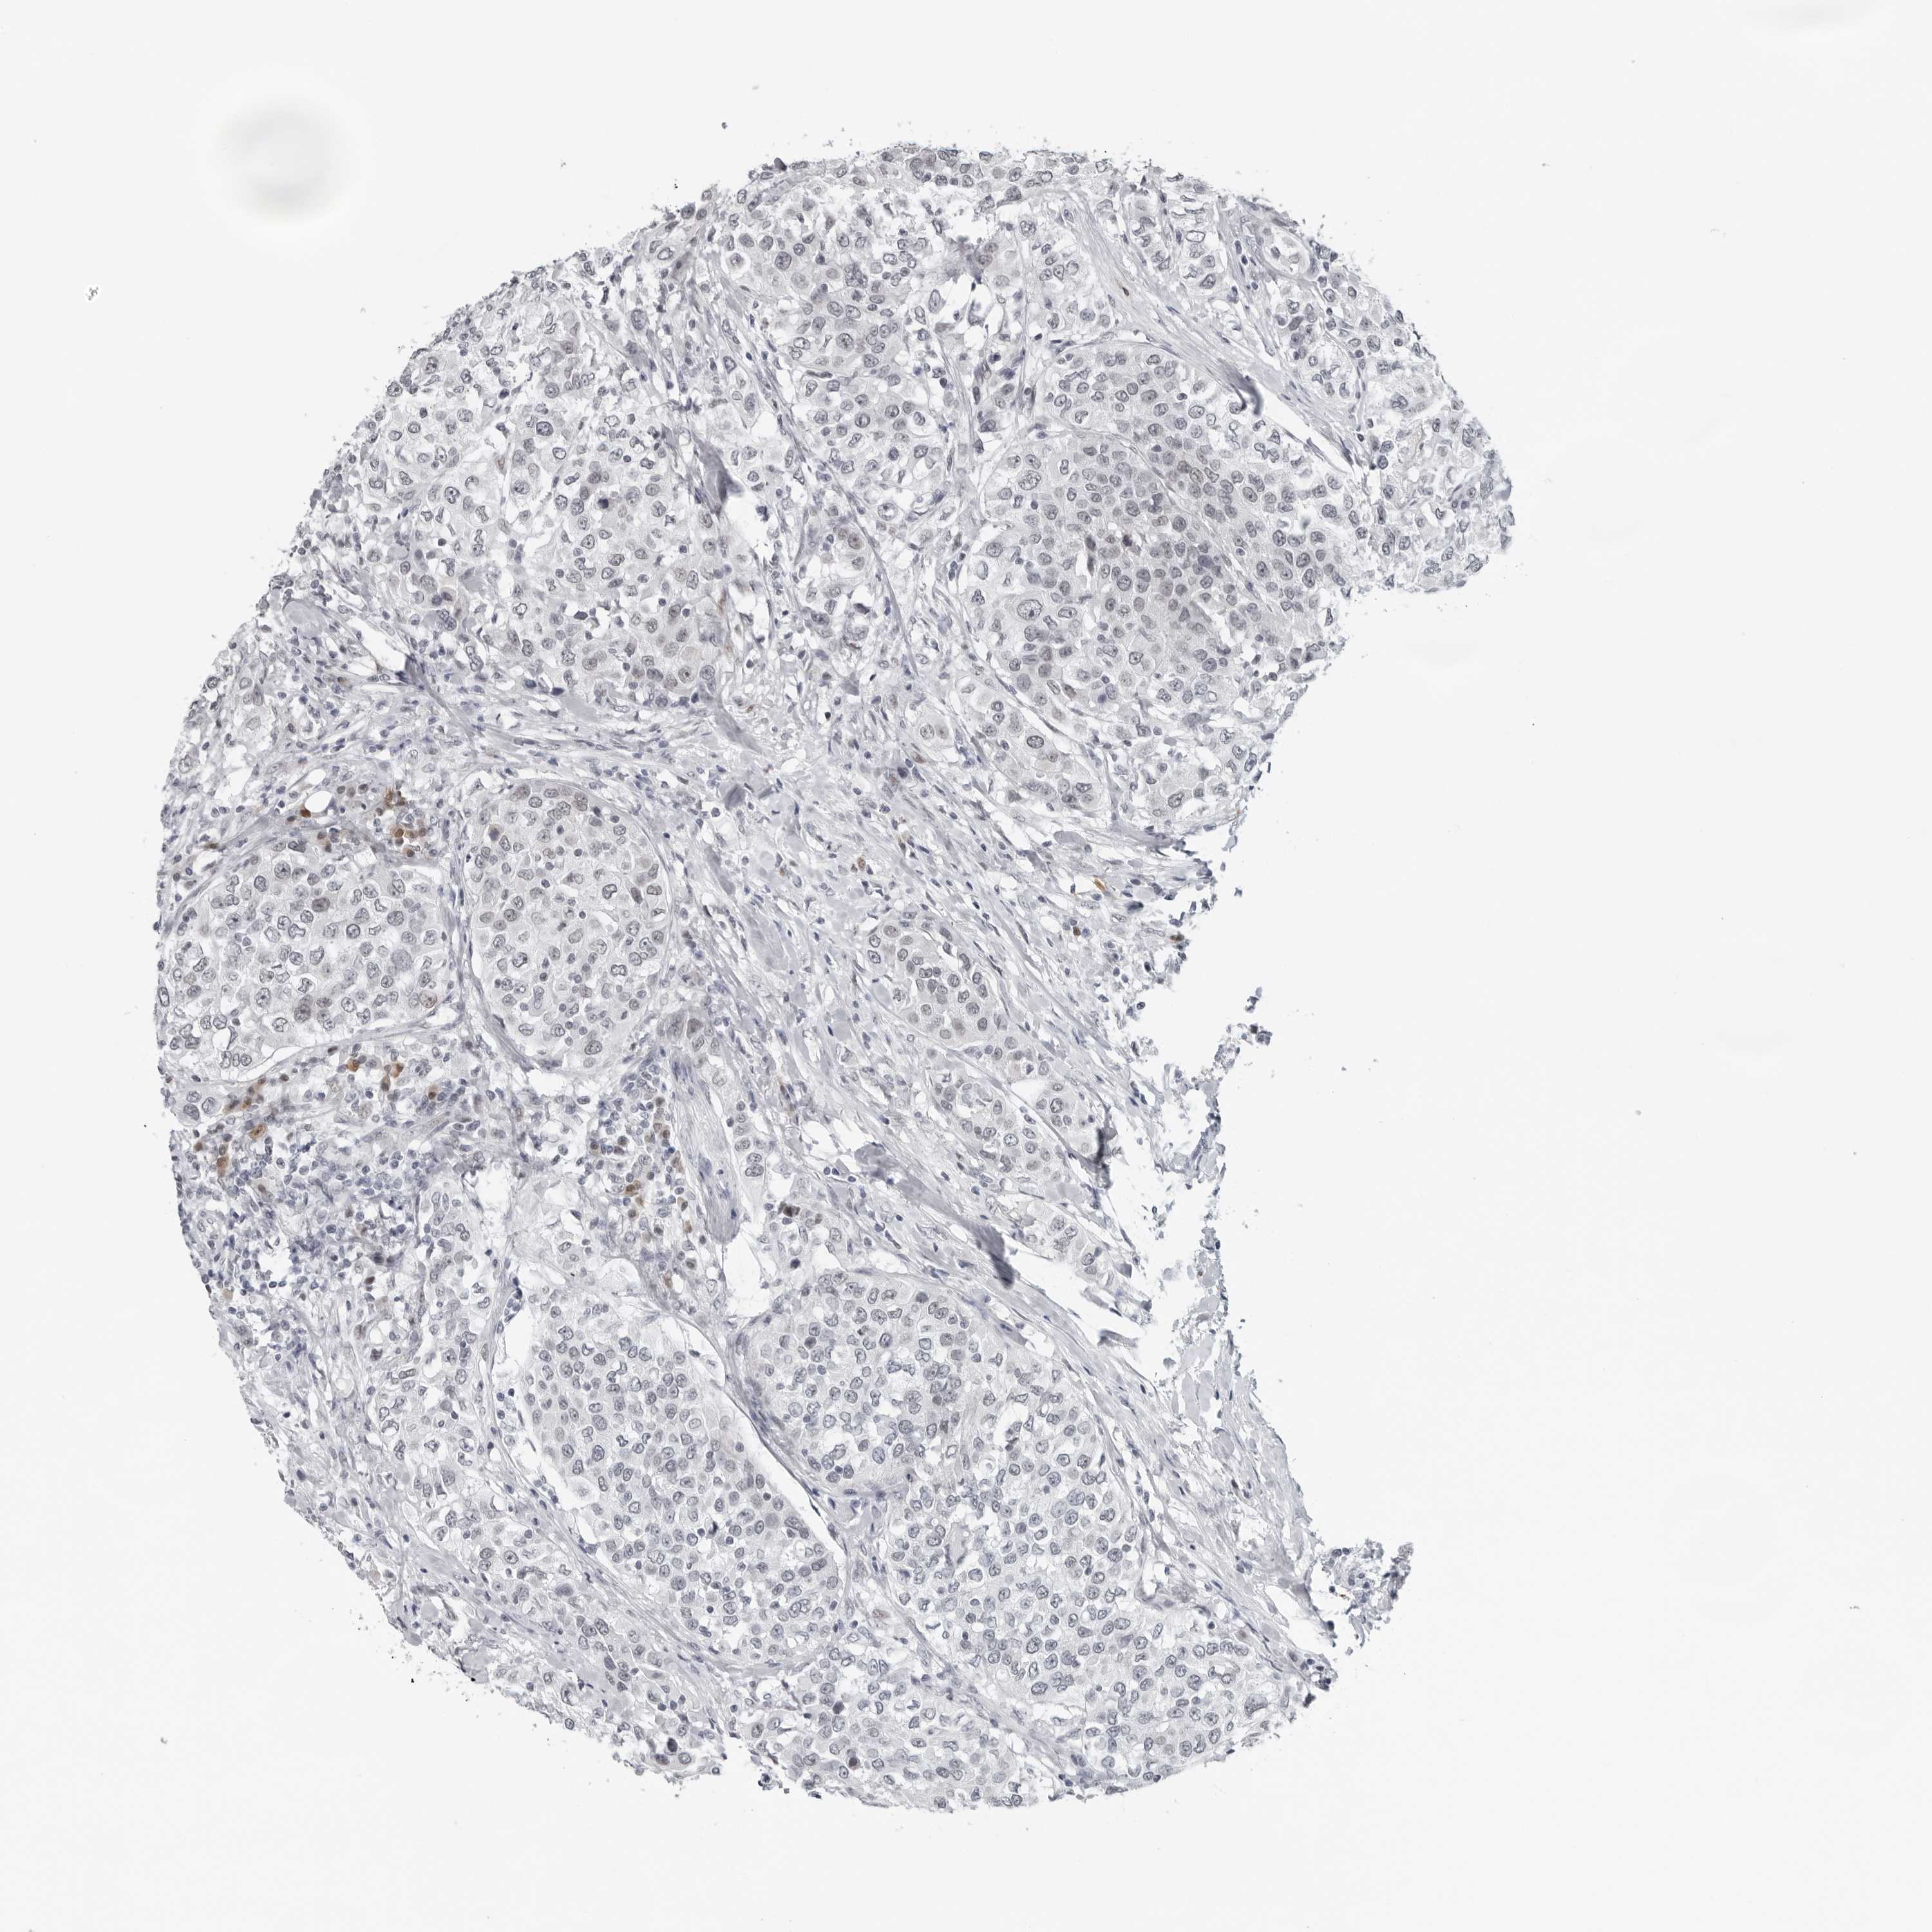

UROTHELIAL CANCER - Protein expressioni

A mouse-over function shows sample information and annotation data. Click on an image to view it in a full screen mode. Samples can be filtered based on level of antibody staining by selecting one or several of the following categories: high, medium, low and not detected. The assay and annotation is described here.

Note that samples used for immunohistochemistry by the Human Protein Atlas do not correspond to samples in the TCGA dataset.

Antibody stainingi

Antibody staining in the annotated cell types in the current human tissue is reported as not detected, low, medium, or high, based on conventional immunohistochemistry profiling in selected tissues. This score is based on the combination of the staining intensity and fraction of stained cells.

Each image is clickable and will lead to virtual microscopy that enables deeper exploration of all samples and also displays staining intensity scores, fraction scores and subcellular localization as well as patient and tissue information for each sample.

Antibody HPA024313

Antibody HPA027983

Antibody HPA028628

Urothelial carcinoma, High grade